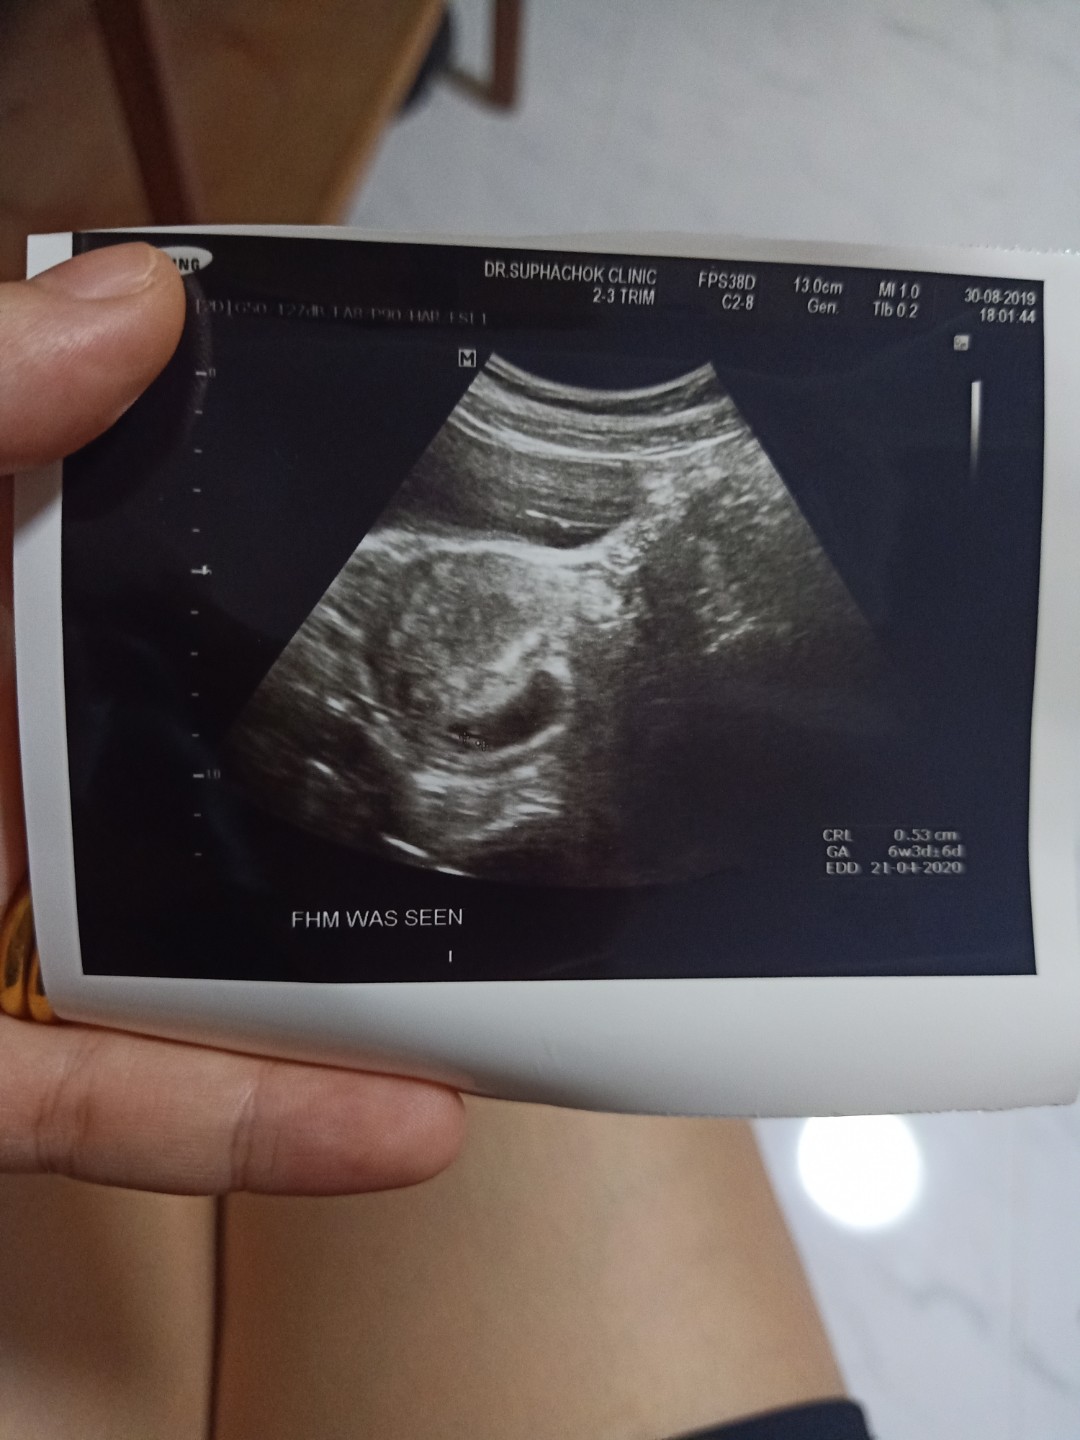

วันนี้เลือดออกและไปอัลตร้าซาวมาค่ะ

ครั้งที่แล้ววันที่19/3 เราไปหาหมอ แต่หมอซาวให้แต่ไม่เห็นอะไรเลยค่ะ วันนี้ไปอีกพบถุงการตั้งครรภ์ค่ะ ดีใจมาก แต่ก็แอบกลัว อยากถามแม่ๆว่า จะเห็นน้องได้ตอนไหนค่ะ